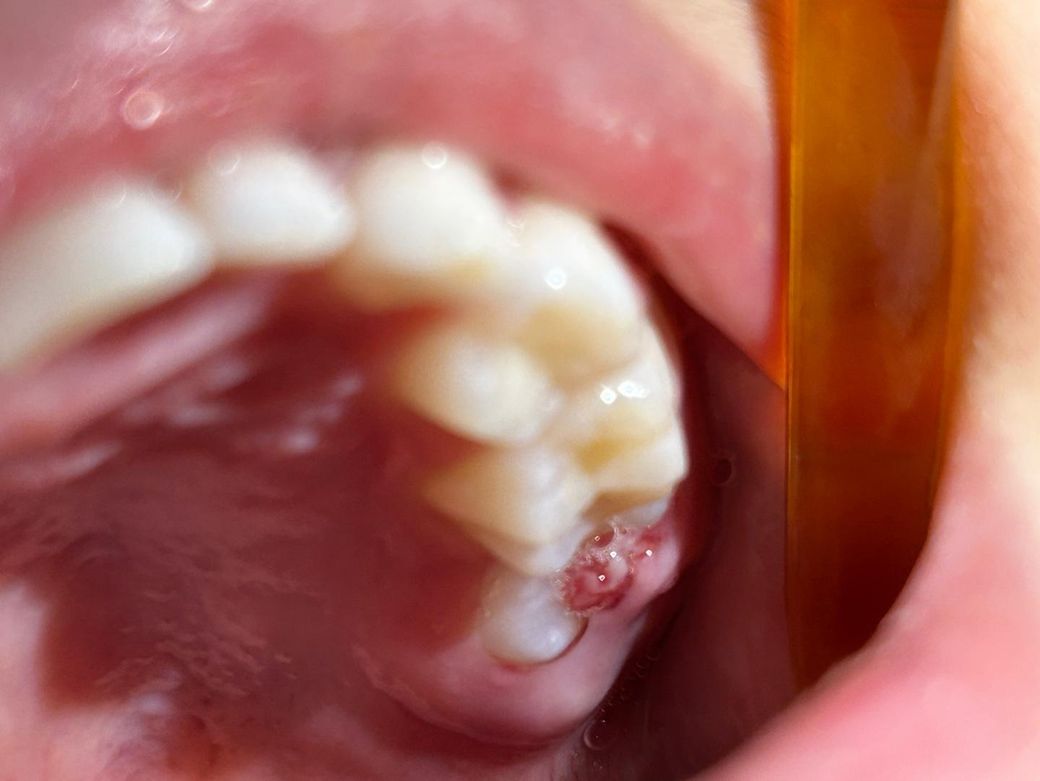

이 옆에 살이 튀어나왔는데 괜찮은건가요?

어금니 맨 안쪽에 이가 하나 올라와있네요.칫솔로 건드려보면서 이를 닦아봤는데 아프진않대요.

아랫니 10개,윗니 11개가 났어요. 아직 이가 다 올라오지않았는데 이가 나면서 자연스런 현상인건가요?

위치상 두번째 큰 어금니이고요 치아가 나오면서 잇몸을 밀고 올라오며 잇몸이 살짝 붓고 찢어진 것 같습니다 해당부위 위생관리만 잘해주면 될 것 같습니다